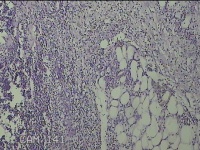

性别

男

年龄

56岁

临床诊断

右侧腋下结节

一般病史

标本名称

大体所见

灰白粉红色组织2.3x2x0.8cm一块,表面带梭形皮肤2.3x2cm,皮下见结节2x1cm一个,结节部分已切开,见结节呈囊性,囊内有少许灰白色角化物,囊壁厚0.1cm。

炎性病变。